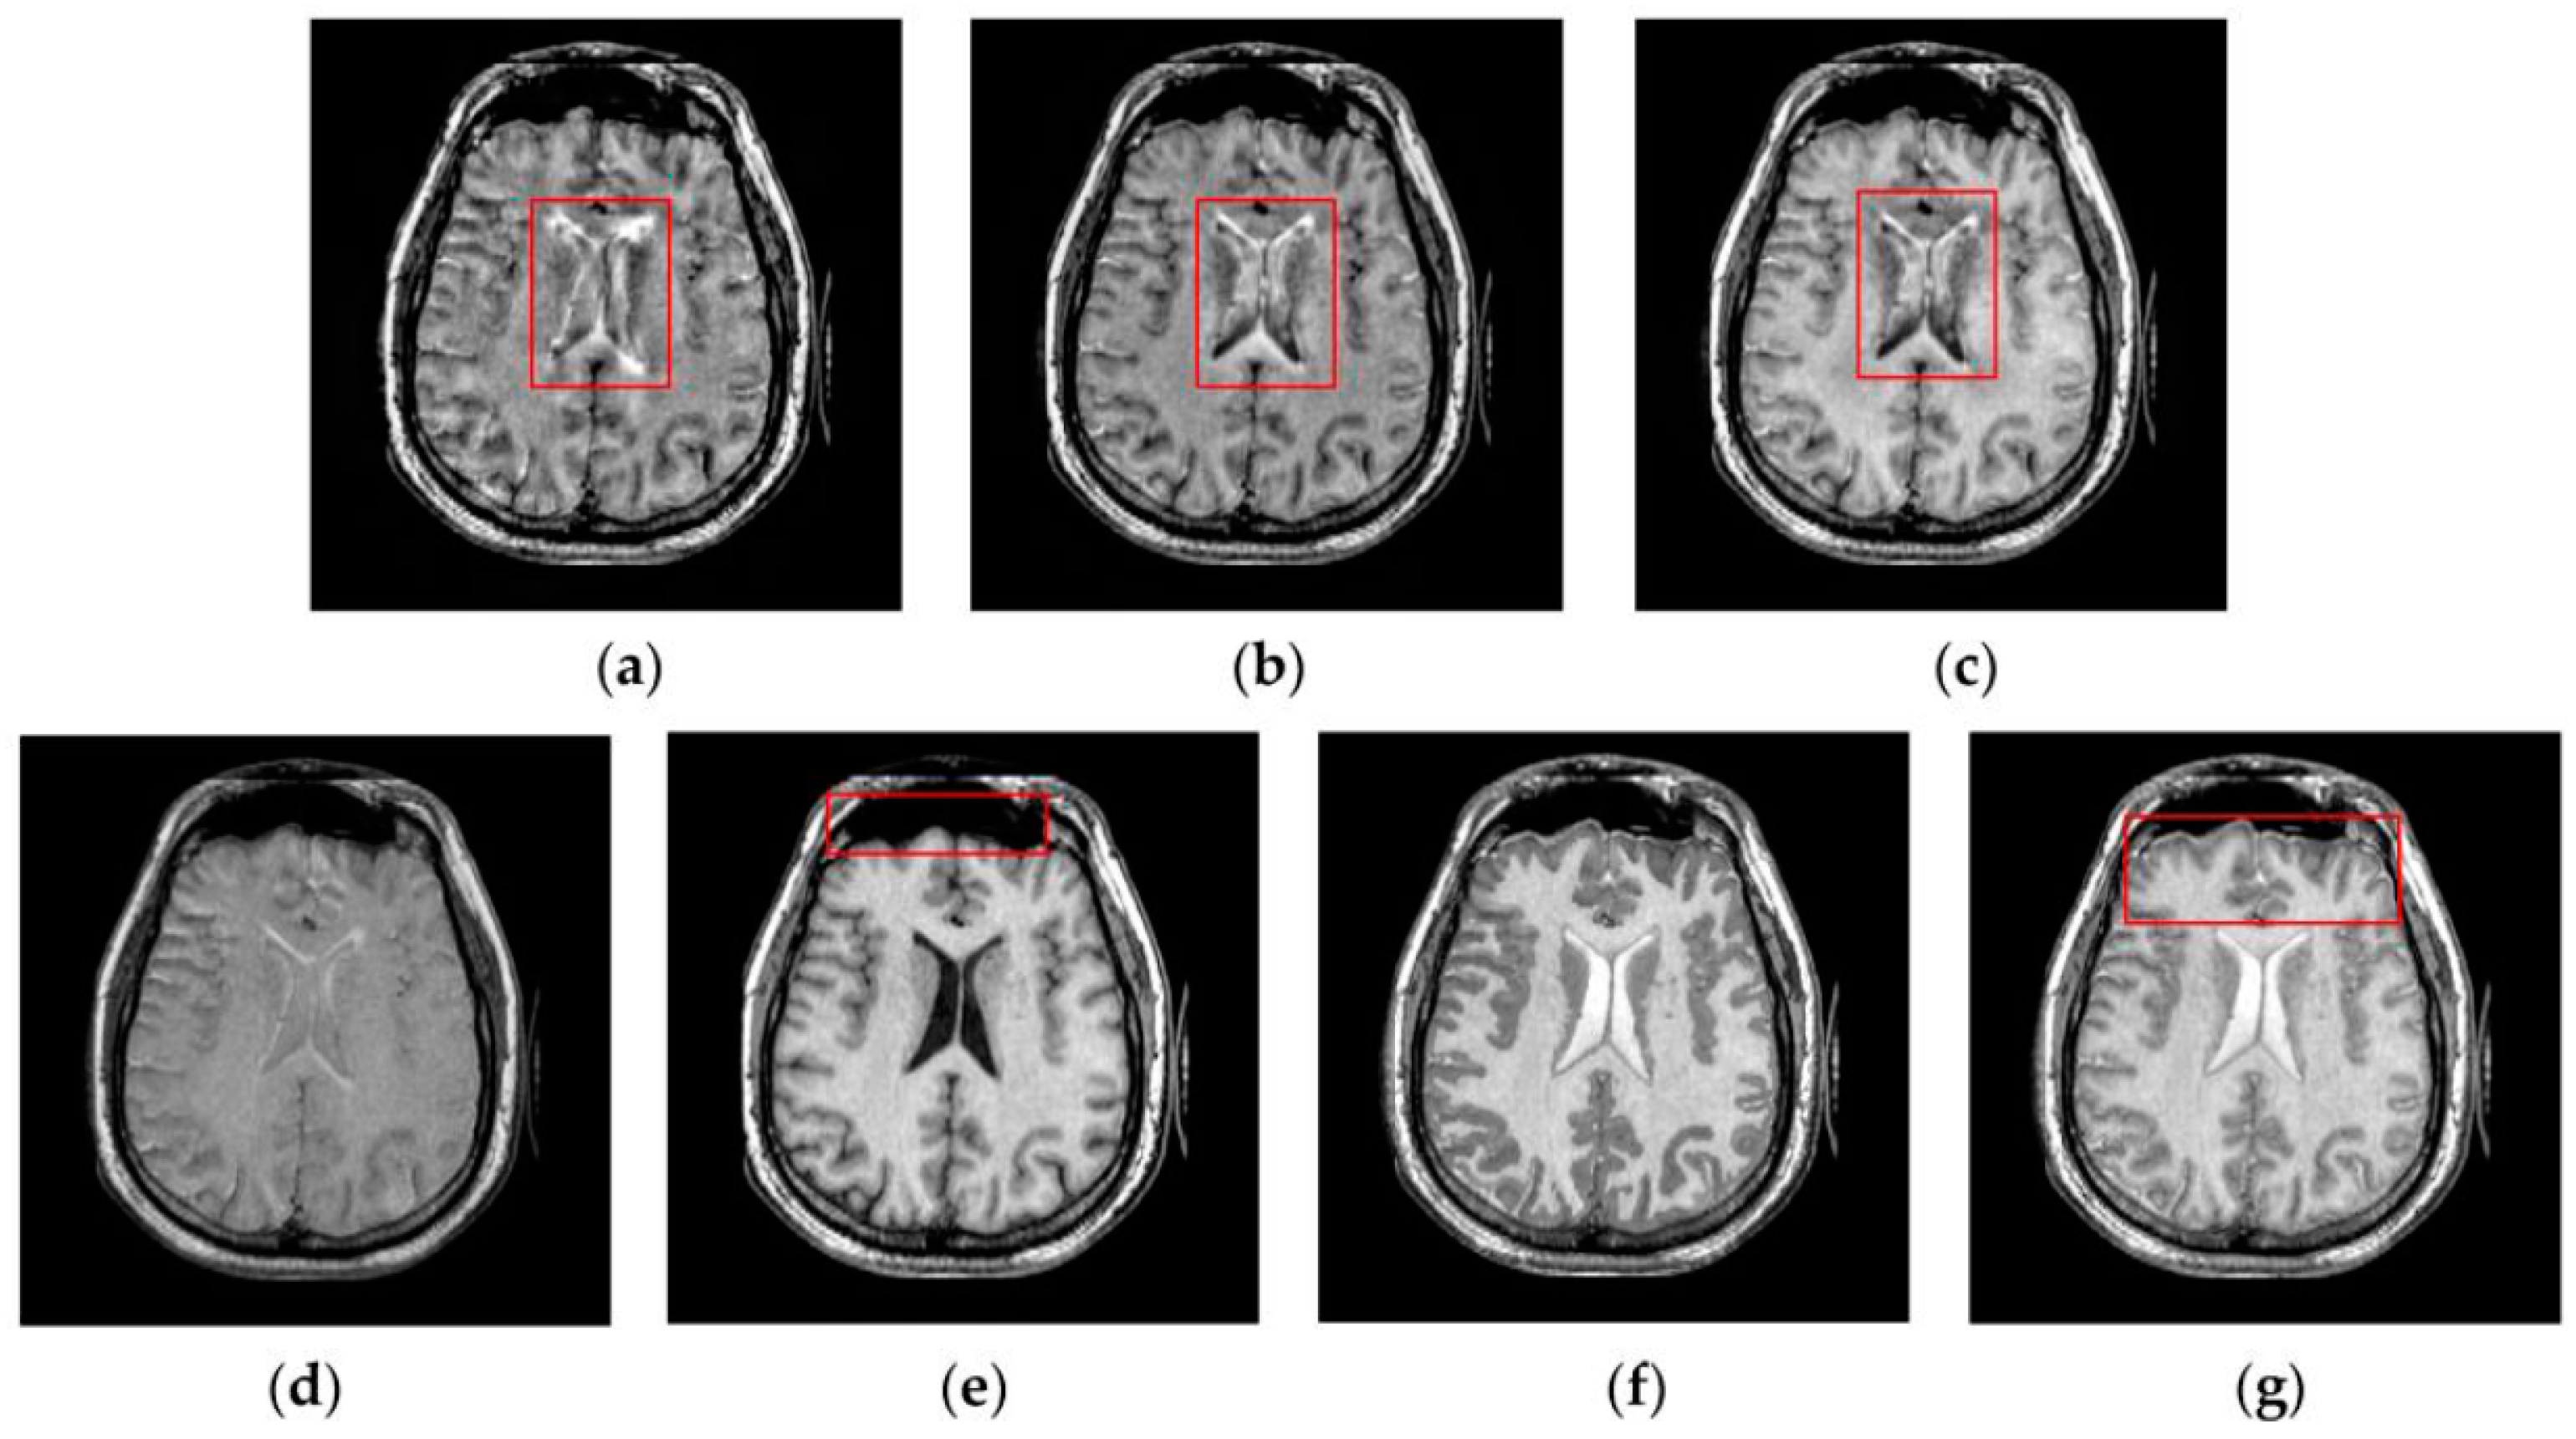

Figure 7, Figure 8, Figure 9 and Figure 10 show the fused results for the evaluated seven methods operating on such medical image pairs as Groups 1, 2, 4 and 5 shown in Figure 6, respectively. The observation from Figure 7, Figure 8 and Figure 10 shows that the DWT, NSCT and NSCT-SR methods introduce artifacts as well as false information in the fused results as indicated by the red boxes, which will greatly influence the quality of the fused images. Meanwhile, it is shown in Figure 7 and Figure 9 that the above three fusion methods cannot preserve image details well in that they produce the obvious distortion of image details marked by the red boxes in the fused results. The m-PCNN method cannot maintain the luminance of the fused results and it produces such low-contrast fused images that some important image details are difficult to identify, which is very disadvantageous for clinical diagnosis. The PCNN-NSCT method and the SCM-F method lead to loss of some important details in the source images to different extent. For example, for Groups 4 and 5, although almost all the details in the MR-T1 images can be transferred to the fused images by the PCNN-NSCT method very well, many details in the MR-T2 images have not been preserved by this method as indicated by the red boxes in the fused images shown in Figure 9e and Figure 10e. For Groups 1, 2, and 5, some image details have been seriously damaged by the SCM-F method as shown by the red boxes in Figure 7f, Figure 8f and Figure 10f.

Figure 7.

Fused results of the evaluated methods for the first group of source images shown in Figure 6a,b: (a) the discrete wavelet transform (DWT) method; (b) the non-subsampled contourlet transform (NSCT) method; (c) the NSCT-SR method; (d) the multi-channel pulse coupled neural network (m-PCNN) method; (e) the PCNN-NSCT method; (f) the SCM-F method; and (g) the SCM-M method.

Figure 8.

Fused results of the evaluated methods for the second group of source images shown in Figure 6c,d: (a) the DWT method; (b) the NSCT method; (c) the NSCT-SR method; (d) the m-PCNN method; (e) the PCNN-NSCT method; (f) the SCM-F method; and (g) the SCM-M method.

Figure 9.

Fused results of the evaluated methods for the fourth group of source images shown in Figure 6g,h: (a) the DWT method; (b) the NSCT method; (c) the NSCT-SR method; (d) the m-PCNN method; (e) the PCNN-NSCT method; (f) the SCM-F method; and (g) the SCM-M method.

Figure 10.

Fused results of the evaluated methods for the fifth group of source images shown in Figure 6i,j: (a) the DWT method; (b) the NSCT method; (c) the NSCT-SR method; (d) the m-PCNN method; (e) the PCNN-NSCT method; (f) the SCM-F method; and (g) the SCM-M method.

By comparison, the SCM-M method not only provides high contrast for the fused images, but also maintains important information from the various source images in the fused results effectively. In particular, the proposed method can preserve fine image details very well as shown by the red boxes in Figure 9g and Figure 10g without introducing artifacts or leading to edge blurring. The above comparisons demonstrate the superiority of the SCM-M method over other compared methods in that the fused images obtained by this method are more clear, informative, and have higher contrast.